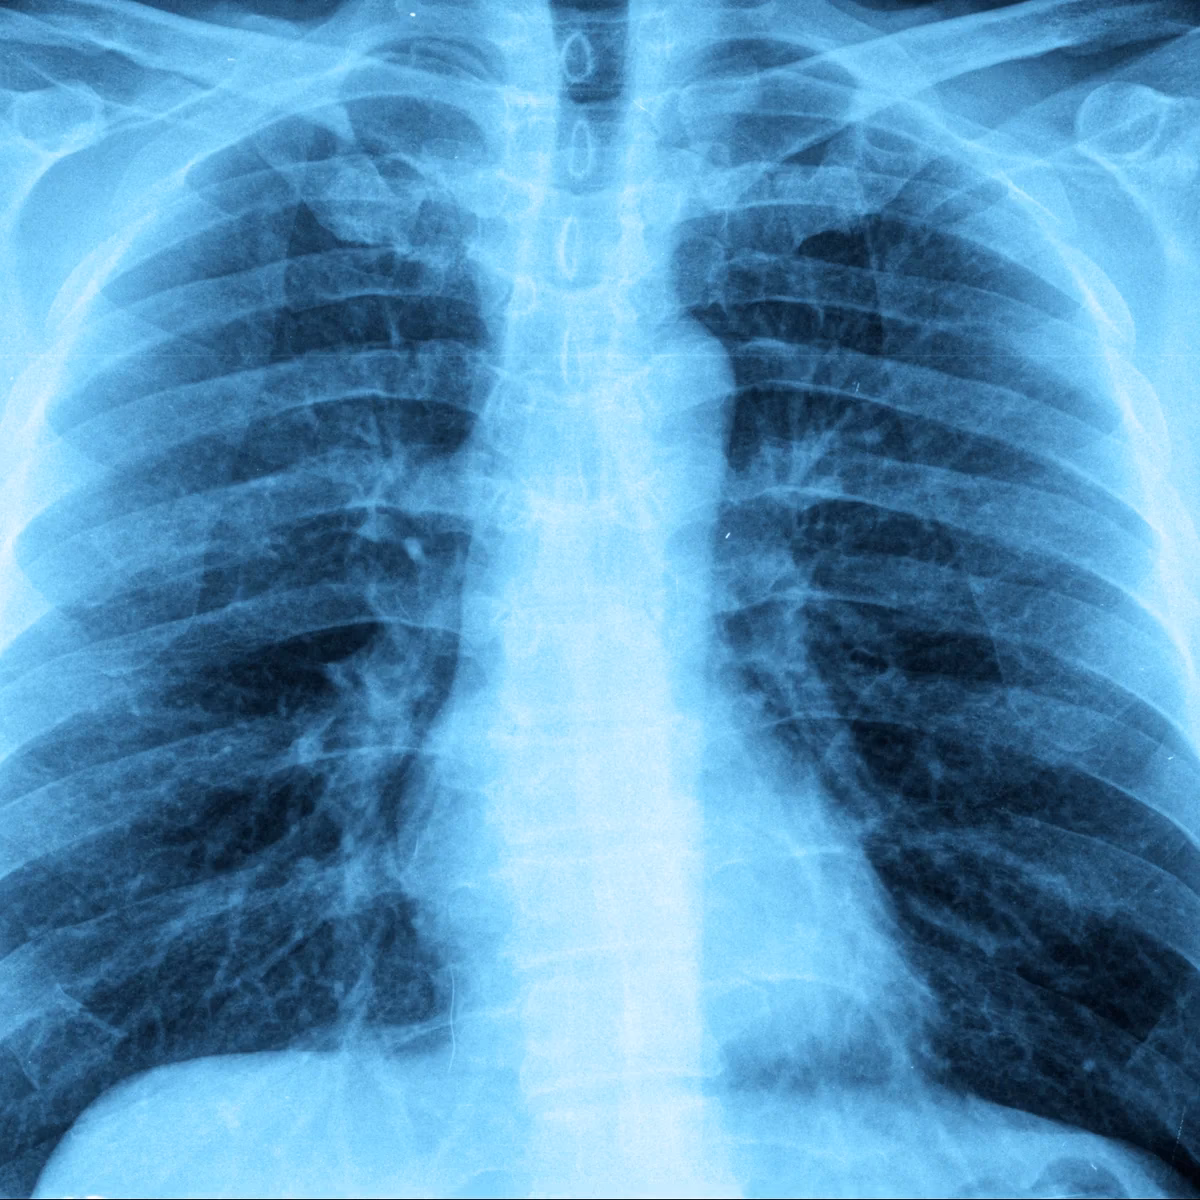

Hvis din læge har mistanke om lungebetændelse, vil han eller hun typisk starte med at lytte på dine lunger med et stetoskop for at høre efter unormale lyde som rallen eller hvæsen. For at bekræfte diagnosen og vurdere alvorligheden, kan flere undersøgelser være nødvendige.

| Røntgenbillede af brystkassen | Dette er den vigtigste undersøgelse for at stille diagnosen. Billedet kan vise betændelsesforandringer og væske i lungerne og afsløre, hvor udbredt infektionen er. |

Hvorfor skal jeg til en opfølgende røntgenundersøgelse?

Din læge vil ofte anbefale et opfølgende røntgenbillede 6-8 uger efter behandlingsstart. Dette er for at sikre, at betændelsen er helt forsvundet, og at der ikke er andre underliggende problemer i lungerne, som kan have forårsaget infektionen.